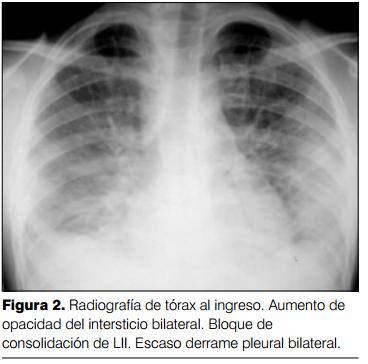

Radiografía de tórax: Aumento de opacidad del intersticio bilateral a predominio basal. Bloque de consolidación de lóbulo inferior izquierdo. Derrame pleural bilateral escaso. Silueta cardíaca normal. No adenomegalias mediastinales ni hiliares (figura 2).